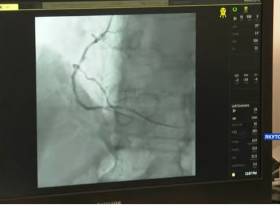

Впервые в кардиососудистом центре медики провели уникальные операции по эмболизации маточных артерий через артериальный доступ при миоме матки с помощью ангиографической установки, сообщили ЯСИА в пресс-службе главы и правительства региона.

«Эмболизация – это один из современных методов лечения миомы матки. Малотравматичный метод позволяет наиболее бережно проводить вмешательство. Операция длится не более одного часа, проводится под местной анестезией, общий наркоз не применяется. Прооперированы четыре пациентки, все операции прошли успешно», — рассказал главный врач Республиканской больницы № 1 – Национального центра медицины Станислав Жирков.

Станислав Жирков отметил, что двум пациенткам операции проведены лучевым доступом, что позволяет активизировать больных спустя два часа после операции, тогда как при бедренном доступе соблюдается постельный режим в течение суток.

Впервые провести уникальную операцию помог эндоваскулярный хирург, заведующий отделением эндоваскулярных методов диагностики и лечения Научного центра акушерства, гинекологии и перинатологии им. В. И. Кулакова Дмитрий Акинфиев.

Эксперт подчеркнул, что эмболизация маточных артерий является отличным способом сохранения матки там, где раньше таких шансов не было